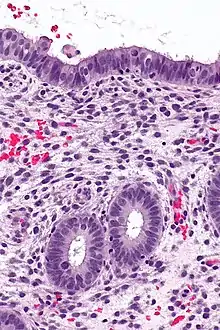

![]() | Serous cystadenoma | Histopathology of serous cystadenoma, with admixed scattered ciliated cells. This case closely resembles normal surface endometrial epithelium of the uterus | Category: Histopathology of ovarian serous cystadenoma | Ovarian cystadenoma |